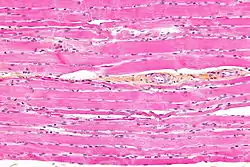

Striated muscle tissue is a muscle tissue that features repeating functional units called sarcomeres. The presence of sarcomeres manifests as a series of bands visible along the muscle fibers, which is responsible for the striated appearance observed in microscopic images of this tissue. There are two types of striated muscle:

Striated versus smooth muscle